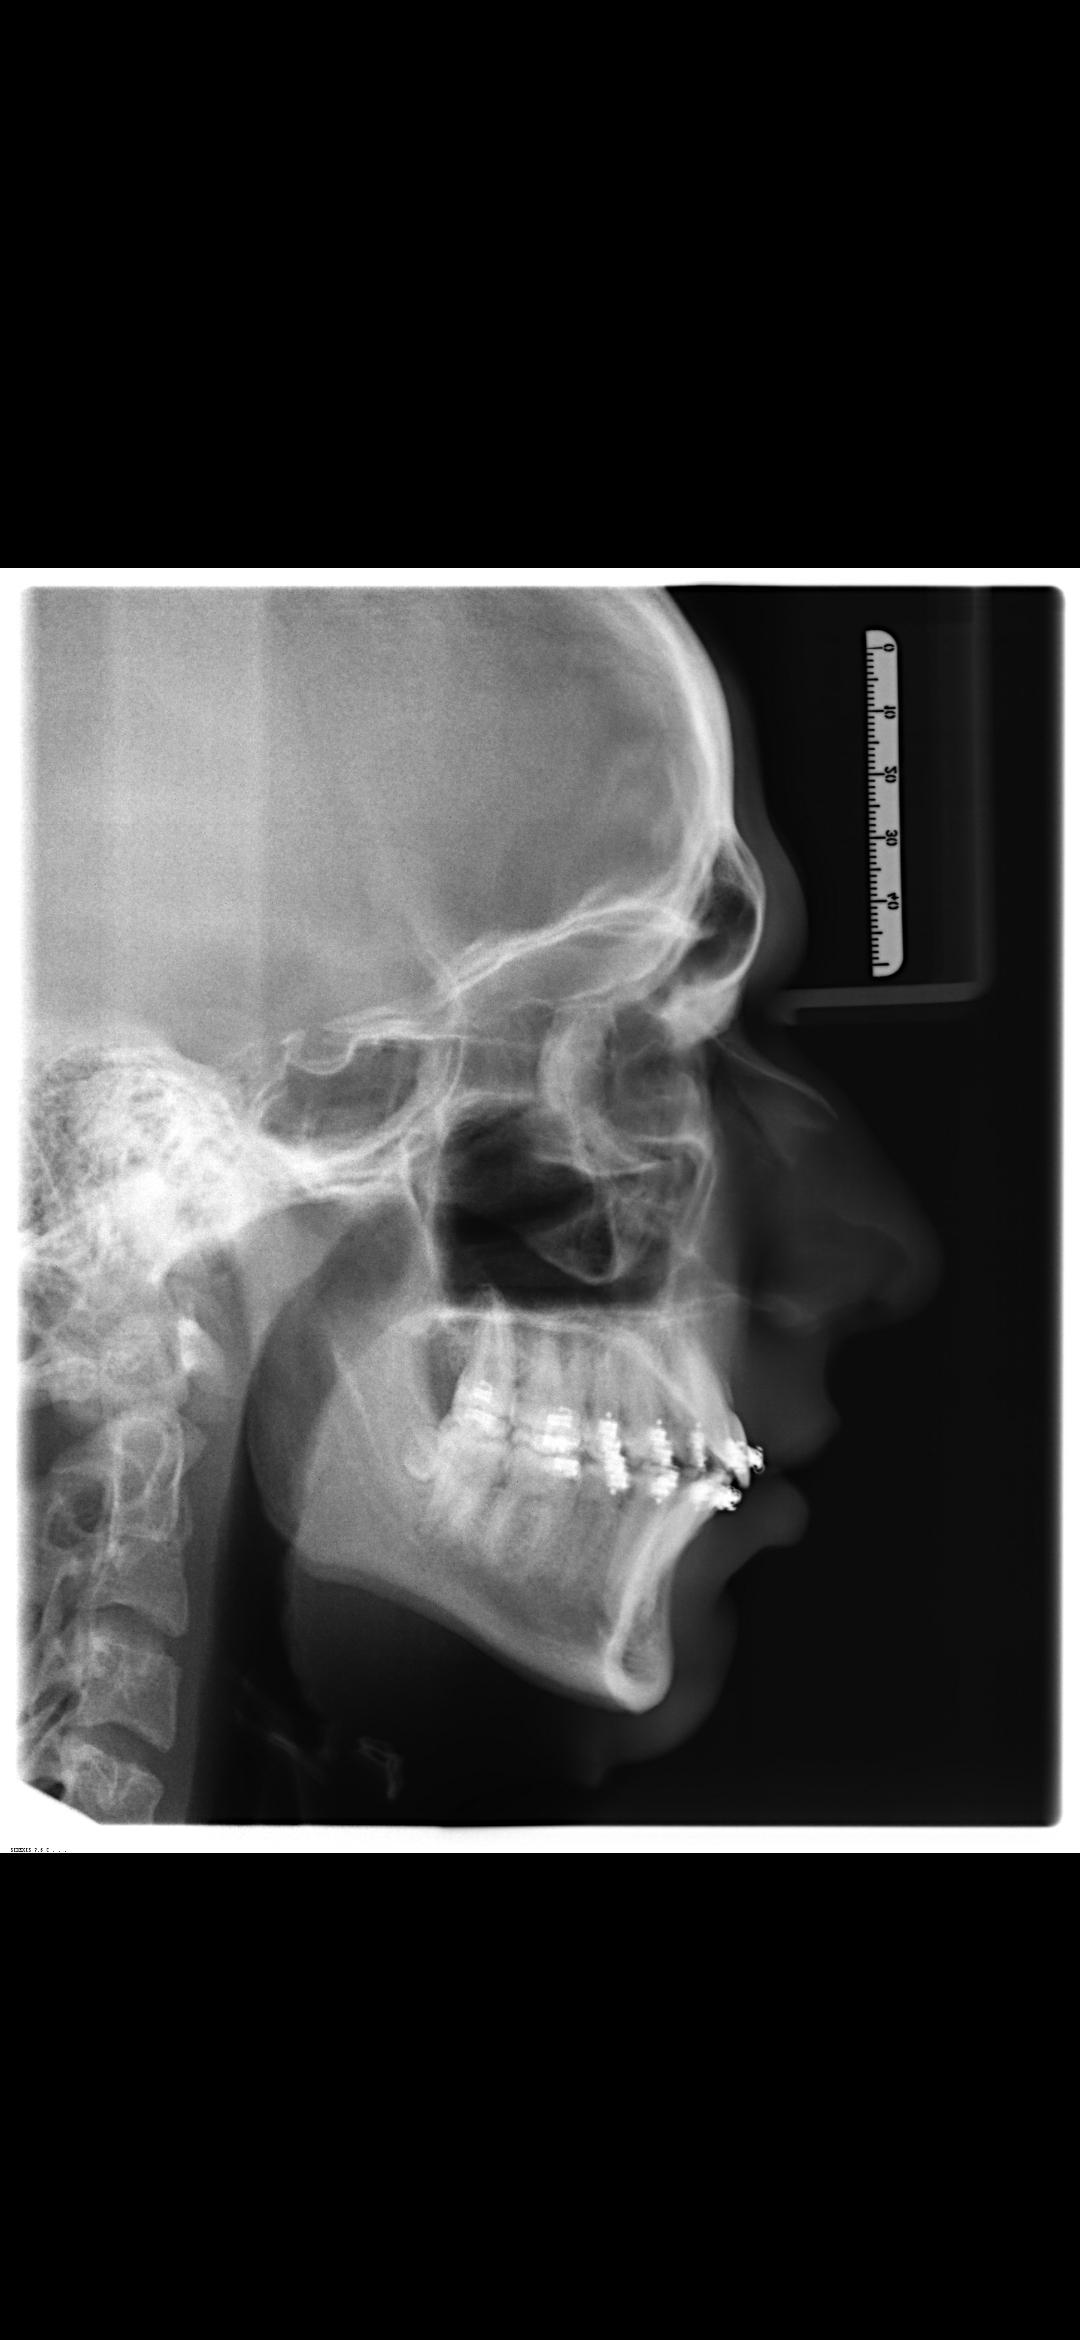

I'm getting bimax surgery + genioplasty in less than 4 weeks performed by Dr. Dr. Kater from Frankfurt am Main (Germany). It'll cost me around 14K€, and I'm 17.

My bite is perfect, but my jaws are still recessed and short, and my chin is recessed too.

I have proof for getting the bimax (1st picture). Can yall look at the other pictures of me and tell me how much it'll ascend me or why it won't?

Now that i have seen pictures, you lower jaw will benefit from it no doubt. About the upper im not so sure.

He needs ccw

He is not too down grown, but a bimax would be more beneficial obviously.

His airway is wide as fuck so there’s no reason he can justify apart from cosmetically.

How much movement are you planning on?